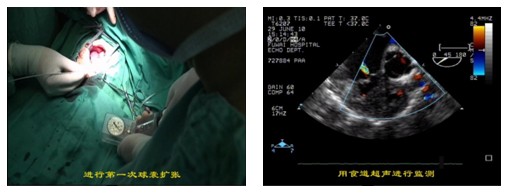

2.新生儿、小婴儿室间隔完整的肺动脉闭锁/重症肺动脉狭窄、此类患儿出生后早期即可出现严重缺氧紫绀、喂养困难、心功能衰竭,任其发展,相当一部分可在出生后1个月内死亡。如能及时解除梗阻不仅能改善患者缺氧症状, 还有利于促进肺动脉和右心室发育。与传统手术及经皮肺动脉瓣球囊扩张成形术相比较, 杂交手术(即经胸肺动脉瓣球囊扩张成形术)具有以下优点:(1) 防止外周血管损伤; (2) 避免体外循环所带来的损伤, 术后恢复快, 监护时间和气管内插管时间缩短; (3) 安全性较高, 扩张过程中如有组织撕裂出血、严重心律失常甚至心搏骤停或其他意外损伤, 可及时在直视下给与处理; (4) 对右心室、肺动脉发育较差患者可同期行体肺分流术, 有利于改善患者预后; (5)如扩张不满意, 合并右心室流出道梗阻时可同期转为体外循环下行右心室流出道疏通术, 避免二次手术。阜外医院资料显示,该技术围术期病死率、并发症发生率低; 中期随访肺动脉瓣再狭窄、肺动脉瓣反流发生率也较低, 大多数无需再干预即达到痊愈水平。因此, 经胸肺动脉瓣球囊扩张成形术是治疗新生儿及婴幼儿室间隔完整型肺动脉闭锁/重度肺动脉瓣狭窄安全有效的方法。

图注:新生儿、小婴儿室间隔完整的肺动脉闭锁/重症肺动脉瓣狭窄hybrid球囊扩张术,术中实时超声检测